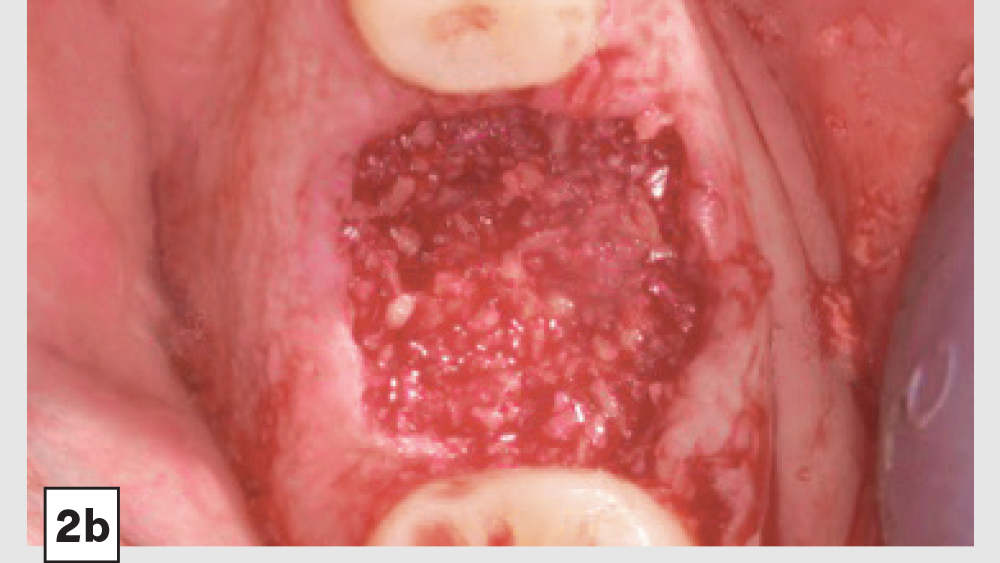

Four-Walled Socket Bone Grafting Technique (Figs. 4a–4d, 5a–5c)

1. Reflection: In most four-walled sockets, a partial mucoperiosteal flap should be reflected to allow for surgical access to the missing buccal plate. This will allow the clinician to place a membrane properly along the buccal plate.

2. Preparation: Ensure there are no soft-tissue remnants within the socket and that bleeding is present. If bleeding is not present, the remaining walls should be decorticated. Care should be exercised around adjacent teeth or vital structures. Bleeding will facilitate early vascularization and initiate the healing process.

3. Graft Material: The graft material (e.g., Newport Biologics Mineralized Cortico/Cancellous Allograft Blend) should be hydrated with sterile saline (0.9% sodium chloride) or platelet-rich fibrin and then gently condensed into the socket. Only small increments of material should be entered into the socket at a time, and a bone-packing instrument should be utilized to condense the bone graft material to avoid air spaces. Usually, when “push-back” of the material is present, the material is packed sufficiently. Care should be exercised to avoid packing the graft material too densely, as this may displace the membrane, interfere with angiogenesis and delay the healing process.

4. Membrane: Because of the missing buccal plate, a longer-acting collagen cross-linked membrane (e.g., Newport Biologics Resorbable Collagen Membrane 3-4) or a PTFE (e.g., CytoSurg Non-Resorbable PTFE Membrane) should be used. The membrane should be trimmed in a modified V-shape (Fig. 5a).6 The narrower part of the membrane should encompass the entire missing buccal wall. Placement of the membrane should be within the confines of the socket, as extending the membrane over the external aspect of any remaining buccal wall will compromise the blood supply. The membrane should cover only the missing buccal wall; the other walls should not have membrane coverage, as this will decrease the healing of the socket. The goal of the membrane is to prevent the soft tissue from repopulating the defect. The wider part of the membrane should be trimmed so that it is slightly larger than the socket opening to allow for placement under the flap.

5. Closure: Closure should be completed with a 3-0 or 4-0 high-tensile suture material (e.g., PGA or PTFE) with a crisscross suture technique. Care should be exercised to avoid suturing through the membrane. Gut sutures (plain, chromic) should be avoided, as they have a compromised tensile strength and incision line breakdown may occur.